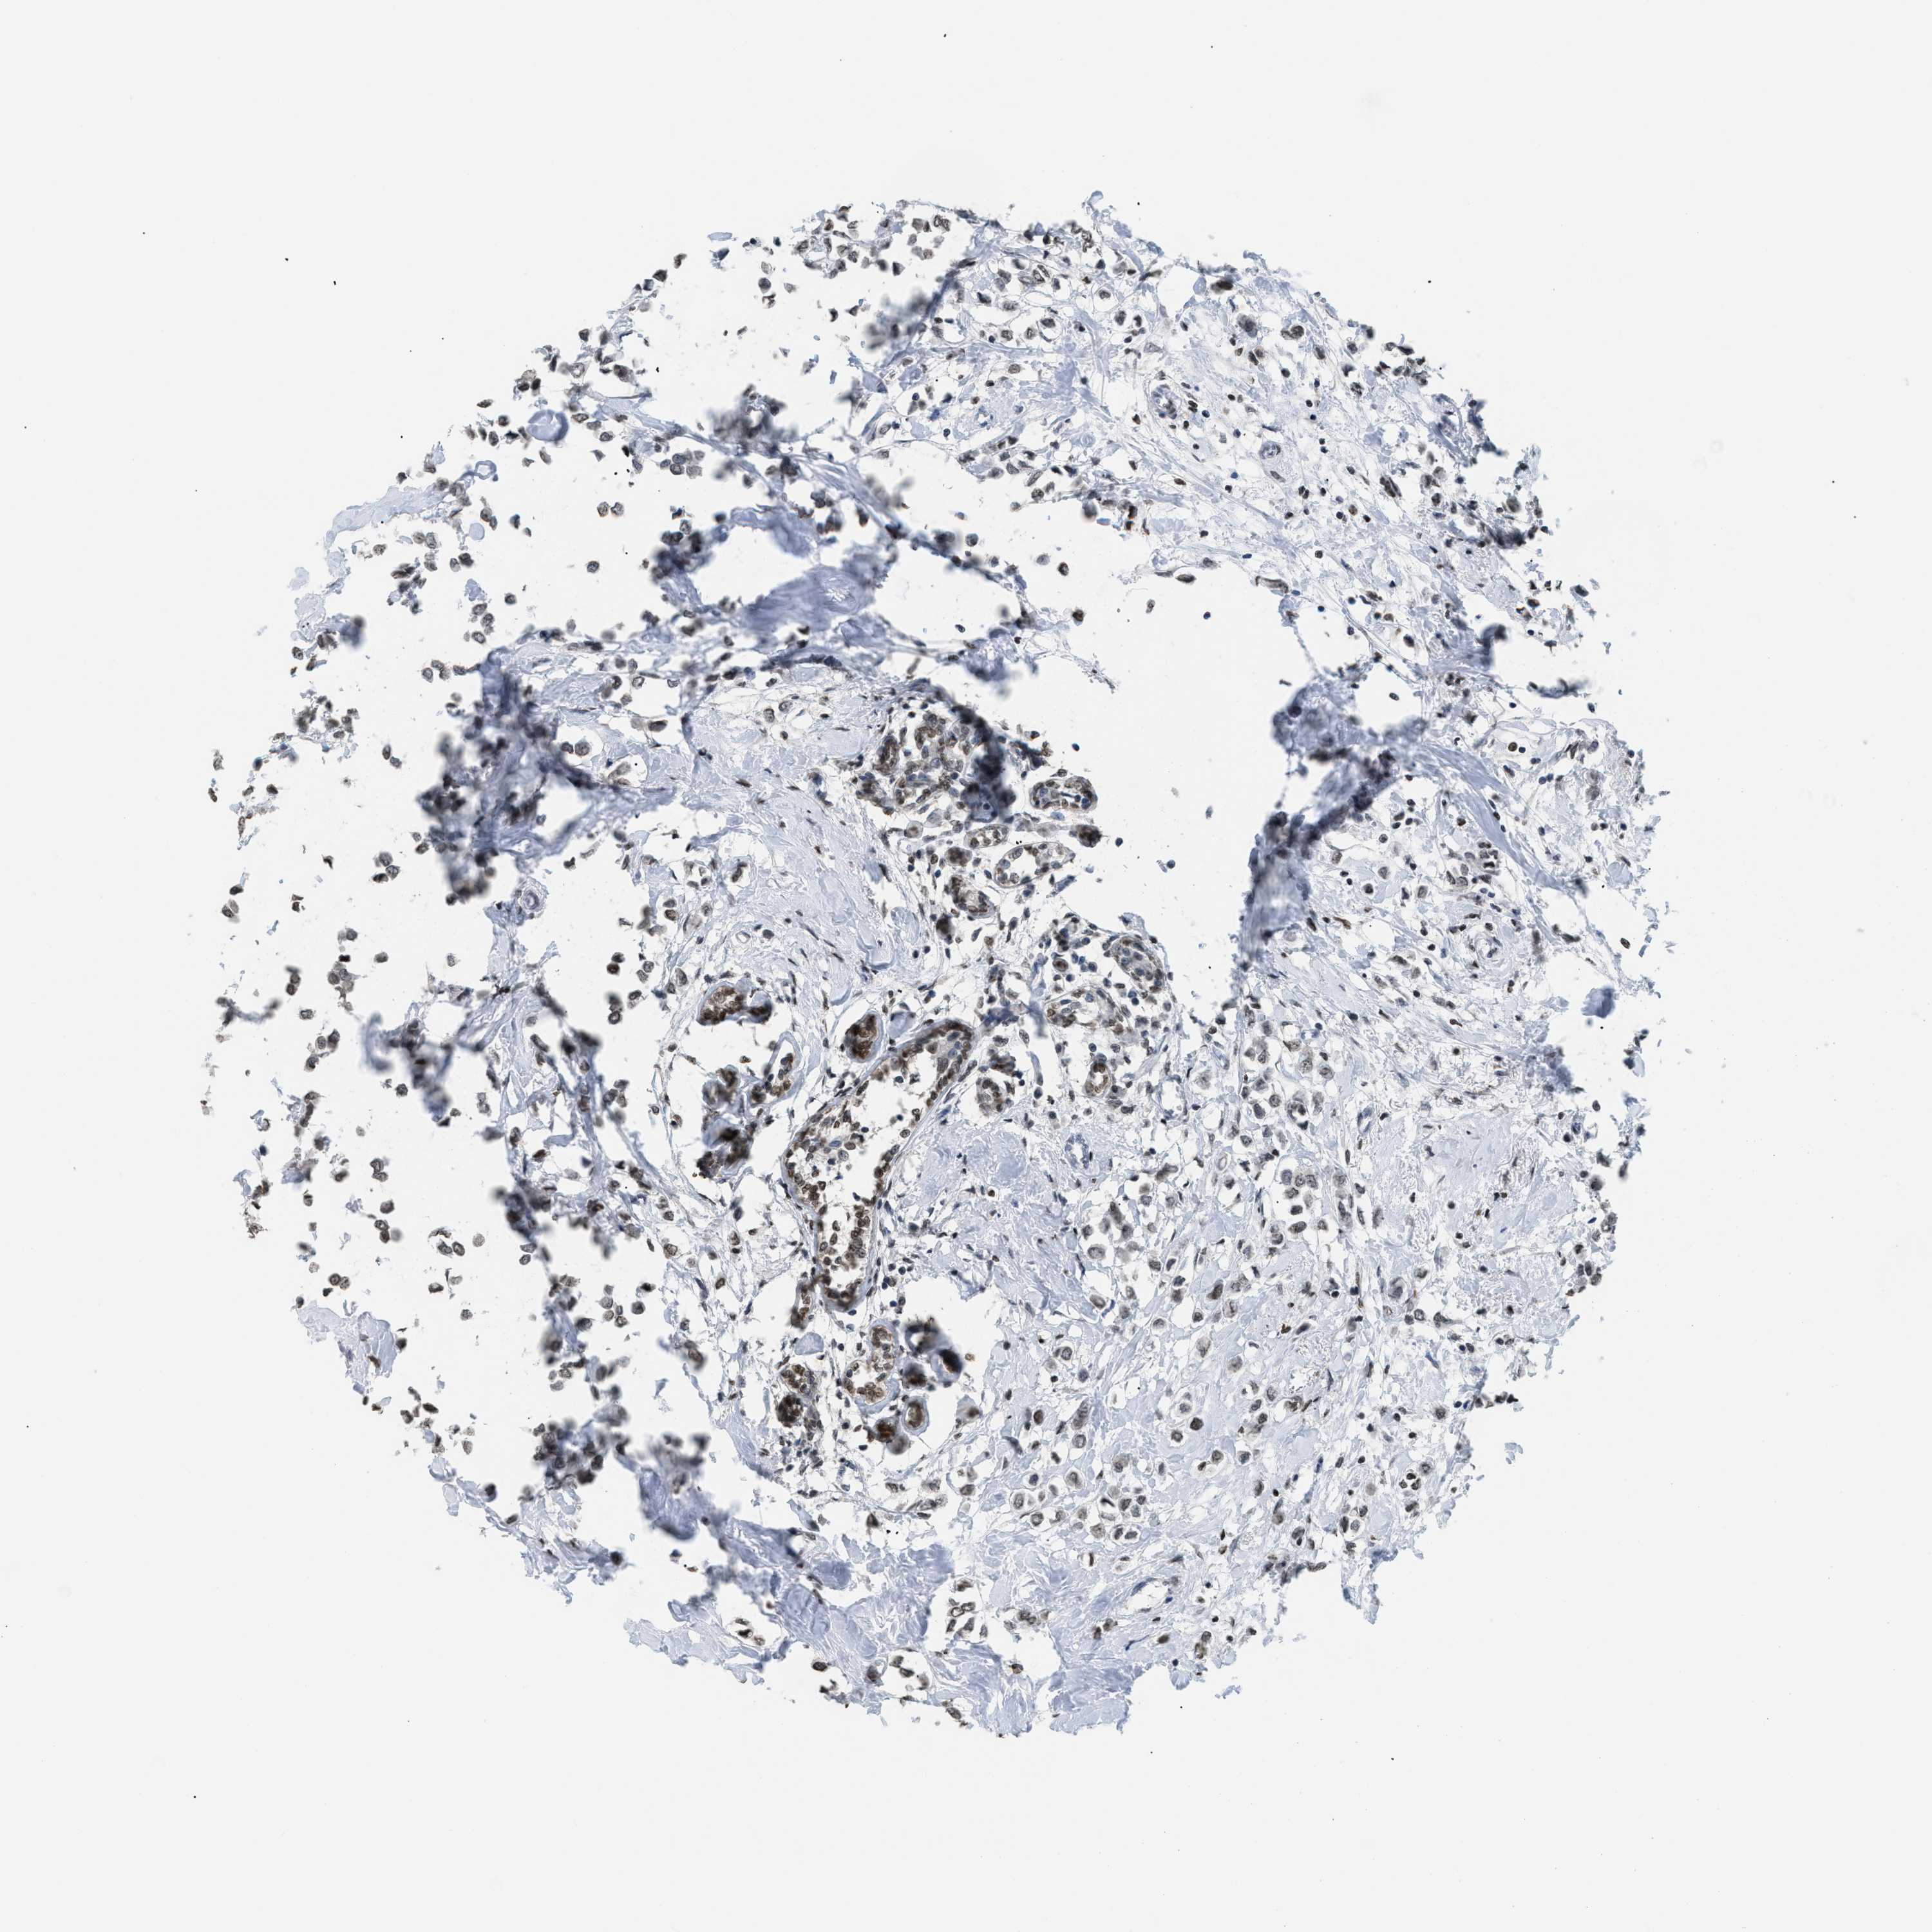

BRCA TCGA BRCA VALIDATION PROTEIN EXPRESSION

ANTIBODIES

AND

VALIDATION